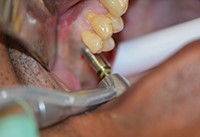

به دنبال پروتکل تجویز شده، یک پانچ بافت هدایت کننده 6.0 میلیمتری برای حذف بافت توپی متمرکز در اطراف سوراخ آزمایشی اولیه مورد استفاده قرار گرفت (شکل 4). اکنون که استخوان تاج در معرض قرار گرفته است، ابتدا استوئتومی بالایی 3.5 میلیمتری (شکل 5)، و سپس استوئتومی گسترده ی 5.7 میلی متری (شکل 6) استفاده شد. به طور معمول، با سیستم OCO، پروتکل اجازه ی پیشرفت از مرحله آزمایشی به قطر نهایی را در یک مرحله به دلیل طراحی منحصر به فرد مته می دهد.

هنگام استفاده از ایمپلنت 6.0 میلیمتری، توصیه می شود تصاعدی عمل کنید تا مته «ترک ناگهانی» را کند کنید و همچنین احتمال داغ شدن استخوان توسط این جهش بزرگ در قطر را کاهش دهید. هنگامی که استئوتومی در محل شماره ی 3 تکمیل شد (شکل 7)، مراحل برای سایت شماره ی 2 تکرار شدند. تنها تفاوت، استفاده از یک لاستیک1.0 میلیمتری O-ring همراه با یک نقطه عمقی 6.0 میلی متری برای نشان دادن عمق مناسب حفاری بر اساس اندازه گیری های CBCT بود (شکل 8).

شکل 5. استئوتومی 3.5 میلی متری پیشین.

شکل 6. استئوتومی 5.7 میلیمتری پیشین.

شکل 7. استئوتومی کامل.

شکل 8. مته حفاری با توقف عمق و O-ring.